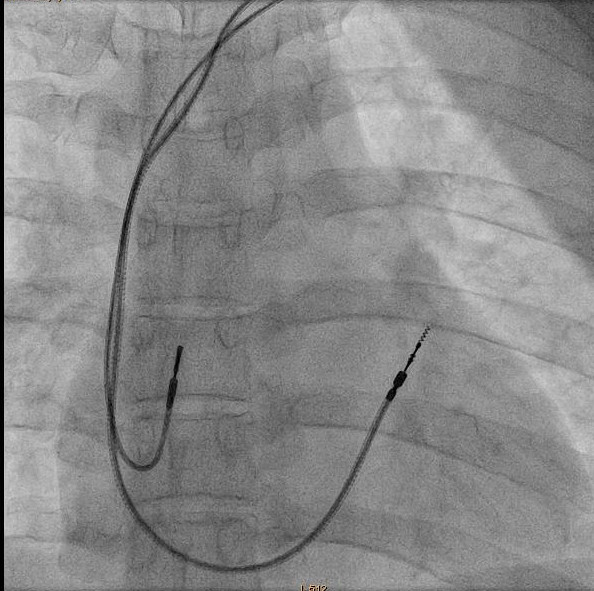

Example

hbp_example.jpg

from Pugazhendi Vijayaraman